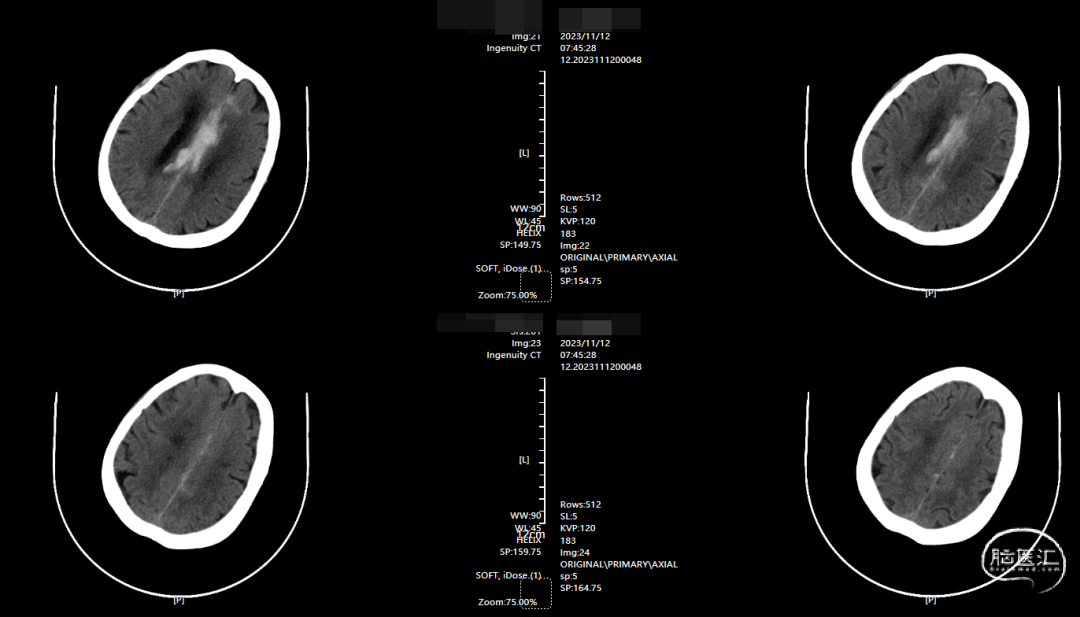

术前影像

CT示纵裂内血肿。